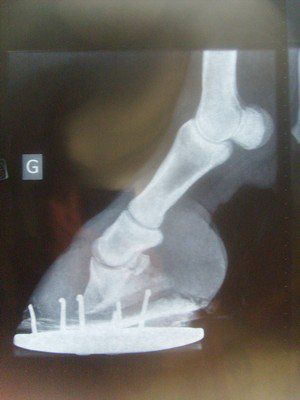

| Dire merci | bonjour je vous présente Quizzy, ponette ONC de 7 ans. ![]() nous l'avons achetée il y a deux ans, débourrée, travaillée. malheureusement, Quizzy est fourbue depuis 5 semaines. 1ers veto et MF, une catastrophe. l'état de quizzy s'est dégradé. j'ai fait appel à un autre veto (pas celui du club) spécialisé et un autre MF. on a fait des radios. bascule très importante de la 3ème phalange aux antérieures (beaucoup plus "légère" sur les postérieurs) ![]() aujourd'hui, quizzy est au box, au foin. c'est dur pour elle qui vivait au pré (je précise qu'il ne s'agit pas d'une fourbure due à l'obésité... elle ne l'était pas... mais plutot d'une fourbure d'effort/exces d'eau froide). pour nous, c'est dur aussi. car on veut y croire et tout faire pour elle mais on n'entend que des "mais elle est foutue, pourquoi tu t'emmerdes", "à ce degré de basculement, plus rien à faire", "tu pourras plus la monter", "t'es dingue d'engager des frais" etc... alors, comme j'ai besoin d'un peu de soutien moral, je fais ce post, pour parler des, je l'espère, progres de quizzy, que nous aimons et pour laquelle nous voulons nous battre. si, parmi vous, certains ont eu des cas de basculemements importants avec issue "positive", les témoignages seront les bienvenus... voila, merci de m'avoir lue.... |

| Dire merci | voilà une radio d'un antérieur....pour vous donner une idée de la bascule (me suis trompée sur le premier post, j'ai mis un postérieur)![]() |

| Dire merci | je sais que la bascule est vraiment grave. pas loin de 20 degrés. .... mais c'est notre ponette et on l'aime. alors que faire ? la condamner de suite ? ou essayer et se battre pour qu'au moins elle puisse retrouver une vie correcte, au pré... c'est vrai que quand je la vois, là, qui après 5 semaines, a vraiment du mal à marcher et se déplacer.... ça fait putain de mal et on se pose des questions... mais là, hier, un nouveau MF est venu. il est très connu dans la région pour tout ce qui est difficile et orthopédique. et j'ai l'impression qu'elle se déplace un peu mieux.... et en plus, faut veiller à son moral. et moi, je suis pas sur place, c'est difficile. je cherche et cherche la meilleure solution.... c'est pour ça que ça me fait du bien d'en parler avec vous car c'est un très très long combat, je le sais bien |

| Dire merci | en plus de la bascule on observe un effondrement des phalanges dans le pied. ![]() Il faudrait abaisser les talons pour que le pied se pose plus à plat qu'en pince. ![]() Et puis courage les troisièmes phalanges semblent saines, non nécrosées. ![]() |